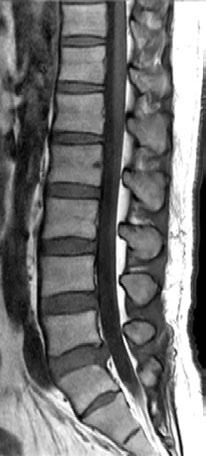

Lumbar Spine T1

Atlas SPEEDER Spine, AiCE + Compressed SPEEDER, Res: 0.35 x 0.35 mm, Scan time: 0:59 min.

Lumbar Spine T2

Atlas SPEEDER Spine, AiCE + Compressed SPEEDER, Res: 0.3 x 0.3 mm, Scan time: 0:57 min.

Lumbar Spine

- Sagital T2

- Resolution: 1.0 x 1.0 mm

- Slice Thickness: 3.5 mm